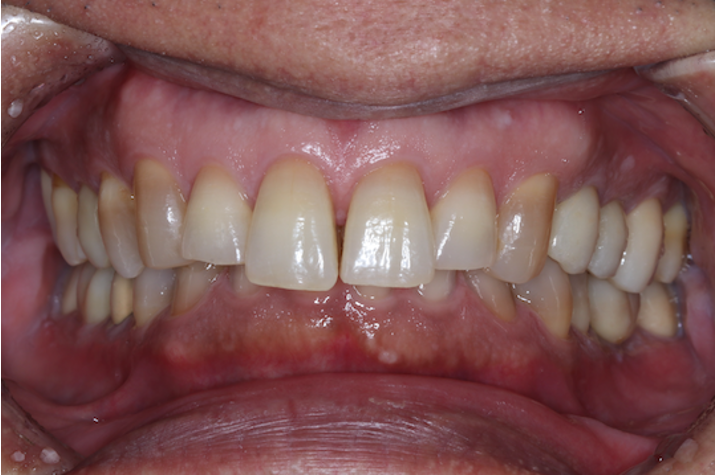

症例①

年齢40代女性

治療期間1ヶ月

治療内容セラミック治療、インプラント治療、ホワイトニング

治療箇所セラミック:左上1番、2番 左下5番、7番 右上1番、2番、3番、4番、5番 右下5番、6番、7番

インプラント:左下6番

治療費用500,000円

インプラント治療、セラミック治療

ホワイトニング